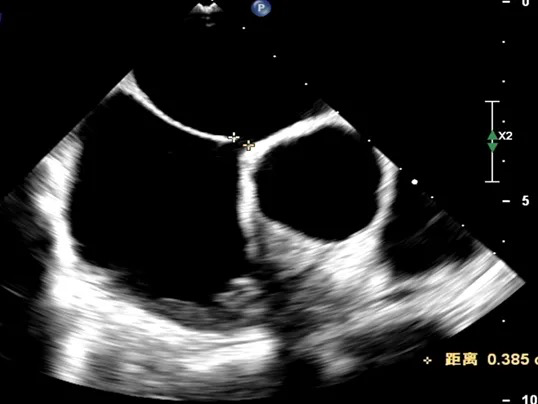

TEE测量缺损大小

肺动静脉CTA未见异常;经食道超声检查明确为小房缺,缺损直径约0.35cm。